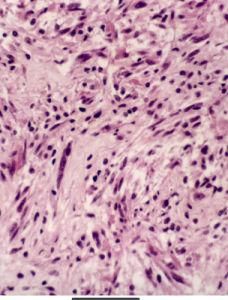

圖1 膠質母細胞瘤膠質母細胞瘤組織表現複雜,形態不一,同一腫瘤的不同部位亦不一致。根據WH0(1990)提出的分類標準,膠質母細胞瘤分為以下兩個組織學亞型:①巨細胞型膠質母細胞瘤。②膠質肉瘤。這些亞型的提出,主要是根據腫瘤的某些比較突出的形態特徵而定,與患者的預後無肯定的相應關係。

腫瘤細胞有多種組織學形態。增殖的腫瘤細胞常以小而深染的圓細胞為主,伴以間變的未分化的纖維性, 原漿性與肥胖性星形細胞,另有大而怪異的來源不明的瘤細胞。腫瘤細胞直徑相差懸殊, 大者可達30μm以上, 小者可能不足10μm。部分腫瘤胞質十分豐富,亦有胞質完全缺如而呈裸核者,核多形性並有較多分裂象。腫瘤壞死區被成堆狹長的腫瘤細胞層層環繞。腫瘤細胞核分裂象相當多見,並可見到單核或多核瘤巨細胞。供血的血管豐富,在腫瘤細胞增殖旺盛的區域內, 可出現血管內皮細胞的異常增殖,形成圍繞的血管球,與腎小球相似,構成膠質母細胞瘤鏡下的另一個特徵。來源於血管外膜細胞的間質纖維增生,嚴重者可成為腫瘤成分。

電鏡下腫瘤細胞大小形狀不一,形態呈原始低分化,核大而周質少, 細胞器稀少但多聚核糖體豐富, 核不規則 核仁突出,常見核分裂象 巨細胞的細胞膜常有摺疊,有時可見大量微絨毛,細胞器多少不固定, 核畸形、 多形、或分葉,高度不規則。巨細胞型膠質母細胞瘤的胞質極為寬闊,充滿大量膠質絲 方向不定,成熟程度不一,線粒體散在其中 糖原豐富,核染色質與核仁突出,毛細血管和小血管內皮增生呈球狀,使血管腔閉鎖 大血管內皮都有增生,多層基膜包繞,大量膠質纖維產生。常見腫瘤細胞有不同程度的壞死,壞死灶中和血管周圍常見巨噬細胞、成纖維細胞和其他炎性細胞。